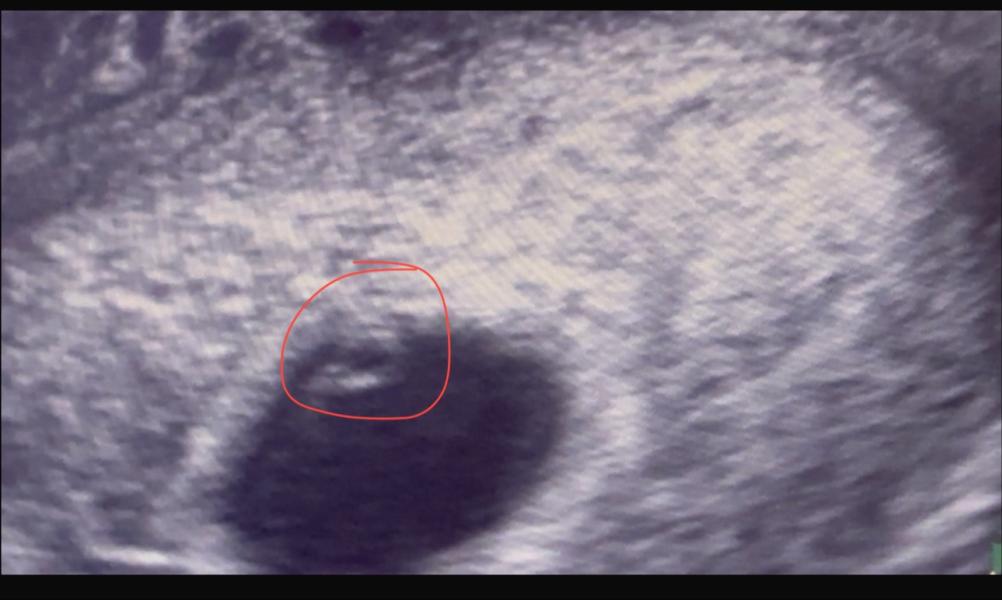

На узи увидела нашу Миру

Сказала ли сердцебиение 💓 есть но оно не очень, плохое. Нам 5 недель и 109-110 и это норма

И да меня на учет не поставили … Хотя сердцебиение есть!

Какое сердцебиение было у эмбриона на сроке 5 недель?